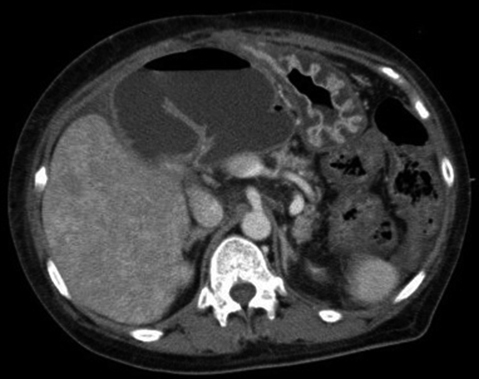

腹部造影CT所見:肝門部尾側に挙上空腸を認め,囊状に拡張していた.一方で肝内胆管は軽度拡張していたものの,胆管結石を疑う高吸収域や明らかな腫瘤性病変は認識していなかった(Fig. 1).

Contrast enhanced CT demonstrated the dilated jejunal limb.